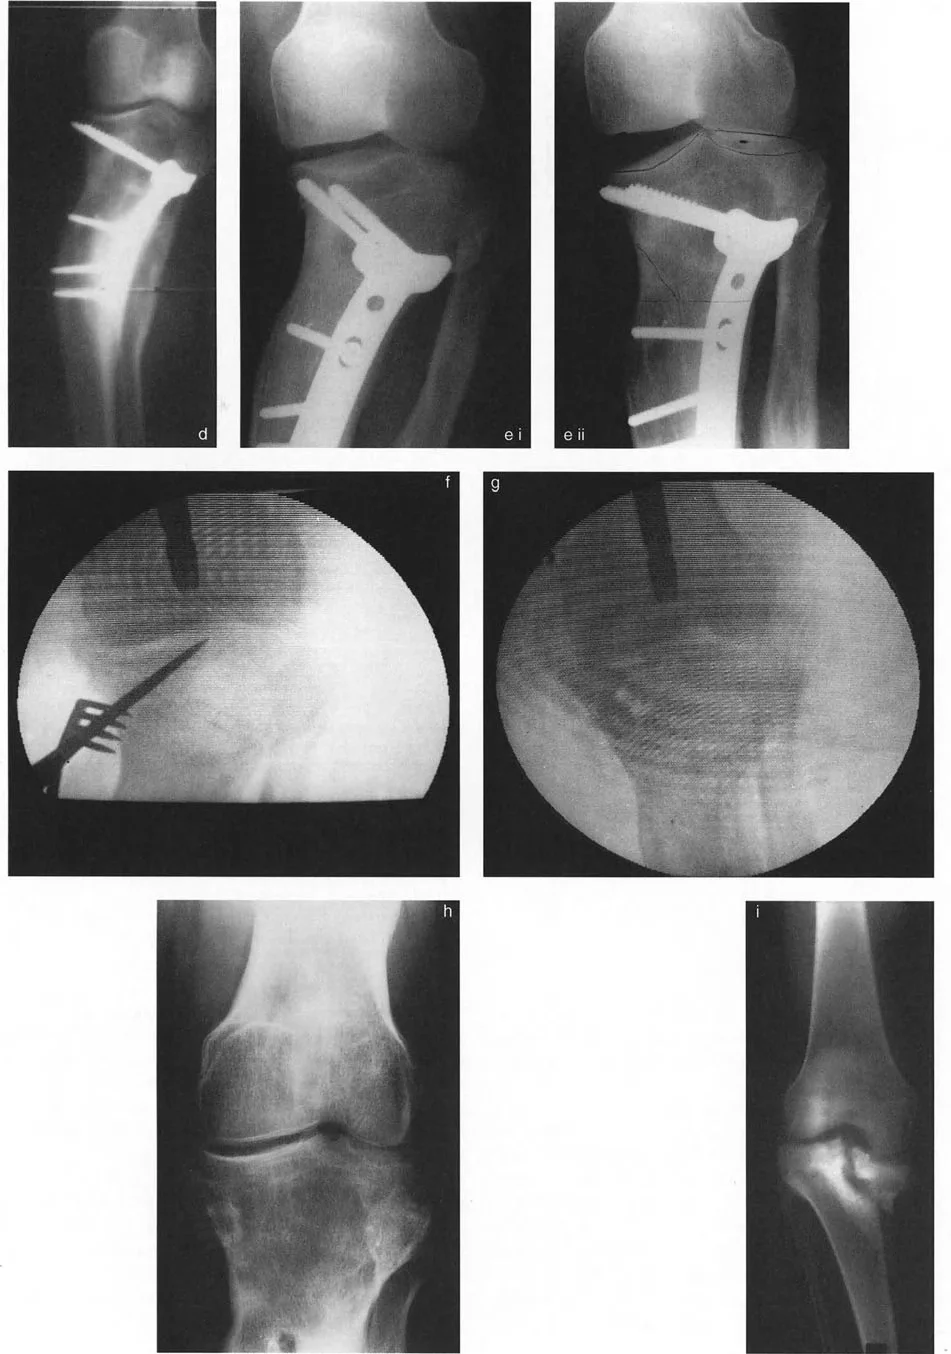

لا تكفي الأفلام القياسية التي تحمل الوزن لهذا التمييز. يجب تقييم كلا مصدري الزاوية التوافقية لخط المفصل المتزايدة عن طريق أشعة الإجهاد التقوسية (varus) والوحشية (valgus)، ويفضل إجراؤها تحت التنظير الفلوري.

- الحد الأدنى للفراغ الغضروفي: يُقاس هذا على جانب التشوه تحت ضغط الانضغاط (على سبيل المثال، تطبيق إجهاد وحشي على ركبة متقوسة لضغط الجانب الوحشي، أو إجهاد تقوسي لضغط الجانب الإنسي). يكشف هذا عن الارتفاع الحقيقي المتبقي للغضروف.

- الحد الأقصى للفراغ الغضروفي: يُقاس هذا تحت إجهاد الشد لتقييم كفاءة الأربطة. إذا انفتح الفراغ المفصلي بشكل مفرط تحت الشد، فإن ارتخاء الأربطة هو عامل مساهم في انحراف المحور الميكانيكي.

إذا تم تحديد زيادة في الزاوية التوافقية لخط المفصل بشكل قاطع على أنها ناتجة عن فقدان ارتفاع الغضروف أو انخفاض العظم الفعلي (وليس مجرد رباط رخو غير كفء)، فيجب دمج هذا المكون المحدد من الانحراف في الحجم الكلي للتصحيح الزاوي.

هذا خطأ شائع يقع فيه الجراحون المبتدئون. سيؤدي الفشل في أخذ هذا الانحراف داخل المفصل في الاعتبار إلى تصحيح ناقص للمحور الميكانيكي أثناء قطع العظم القياسي خارج المفصل (مثل قطع العظم الظنبوبي العلوي أو قطع العظم الفخذي السفلي). قد تصحح العظم، لكن المريض سيظل يمشي مع انحراف في المحور الميكانيكي لأن المفصل نفسه منحرف. بفضل خبرة الأستاذ الدكتور محمد هطيف، يتم تجنب هذه الأخطاء الشائعة من خلال التقييم الدقيق والتخطيط الشامل لكل حالة.

- نهج خط "أفضل ملاءمة" واحد (تخطيط خارج المفصل):

يجب التعامل مع خط مفصل الركبة كخط "أفضل ملاءمة" واحد لعظم الساق القريب فقط إذا لم تكن هناك نية جراحية لتغيير شكل خط المفصل نفسه. هذا يعني أنك تخطط لقطع عظم خارج المفصل (على سبيل المثال، فتح إسفين في عظم الساق القريب) وتقبل التشوه داخل المفصل. يتم رسم خط "أفضل ملاءمة" عادةً مماساً للهضبة عند نقطتها الأكثر تقعراً، أو عن طريق ربط الهضبة غير المشوهة بالحافة المقابلة. ومع ذلك، في الممارسة العملية، غالباً ما يكون خط "أفضل ملاءمة" المفضل هو ببساطة اعتماد خط لقمة الفخذ، بافتراض أن عظم الفخذ طبيعي (قاعدة بالي للاستبدال). - نهج الخطين (تخطيط داخل المفصل):

إذا كان التصحيح داخل المفصل (مثل رفع الهضبة المباشر) قيد النظر لاستعادة تطابق المفصل، فيجب وصف السطح المفصلي بخطين منفصلين - واحد لكل هضبة. يسمح هذا للجراح بحساب بالضبط عدد الملليمترات من الارتفاع ودرجات الميل الزاوي المطلوبة للجزء المنخفض.

التأثير الجراحي: بسبب هذا التسامح الهندسي، يمكن غالباً إعادة محاذاة سوء المحاذاة الناتج عن إزاحة لقمة الفخذ الأحادية أو سوء توجيهها باستخدام قطع عظم الفخذ فوق اللقمي خارج المفصل. لا تحتاج دائماً إلى تقسيم اللقم وإجراء عملية داخل المفصل عالية المخاطر. على النقيض من ذلك، فإن عدم الاستقرار الشديد الناتج عن درجات عظم الساق يتطلب دائماً تقريباً قطع عظم حقيقي داخل المفصل (رفع الهضبة) بدلاً من مجرد تصحيح في الميتافيزيس، لمنع التدمير السريع للمفصل.